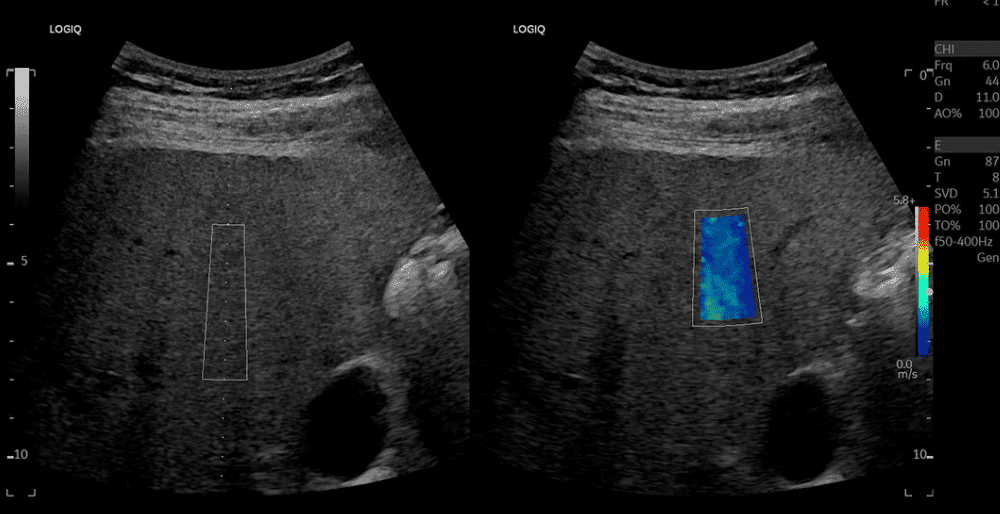

UCAP(초음파유도감쇠매개변수)는 지방이 많아질수록 초음파는 더 빨리 약해진다(attenuation증가)는 점을 이용한 것입니다. 결과를 dB/cm/MHz로 수치화 하여 ‘지방이 얼마나 많은가‘ 를 객관적으로 보여줍니다.  따라서 지방간을 정량적으로 측정할 수 있게 해줍니다.

2D shear Wave Elastography로  조직의 탄성도를 수치화 하여 볼 수 있습니다. ‘단순히 딱딱해 보인다’가 아닌 객관적 데이터를 제공합니다. 추적 검사 시 변화 비교가 용이 합니다.  따라서 간경화 추적관찰, 갑상선과 유방에서 결절 위험도 평가에 보다 객관적 자료를 제공합니다